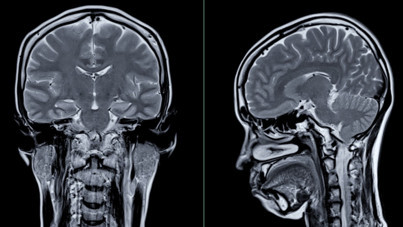

50 yaş altı kadınlar dikkat: Kanser riskini artırıyor Yeni bir araştırma 50 yaş altı bireylerde artan kolorektal kanser riskinin sebeplerinden birini ortaya çıkardı.